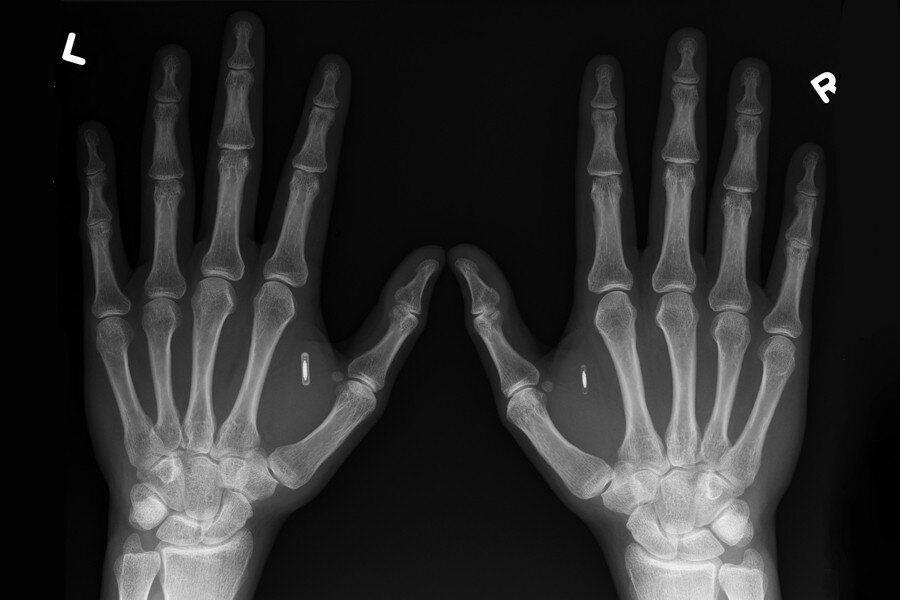

Рентгенологическое обследование кистей рук является неинвазивным и популярным способом диагностики, который не причиняют какого-либо дискомфорта, при этом позволяет достаточно быстро оценить состояние костей, хрящей, выявить различные патологические и воспалительные процессы, переломы, вывихи, изменения в мышцах, лимфатических узлах.

Основными показаниями к проведению данной диагностики является:

• ушибы, переломы, различные травмы;

• болезненные ощущения, отечность, покраснение кисти;

• аномальное строение;

• ограничение подвижности конечности;

• красная системная волчанка;

• подагра;

• появление каких-либо новообразований;

• необходимость выявления костного возраста.

Такая диагностика позволит быстро и эффективно поставить точный диагноз, назначить правильное лечение и предупредить развитие многих тяжелых последствий.

С помощью данного обследования можно выявить достаточно широкий ряд заболеваний, а именно артрит костей, скопление жидкости в суставе, полиартрит, костные разрастания на поверхности суставов, кисты и т. д. И в некоторых случаях рентгенологическое обследование выступает единственным способом оценки течения болезни, эффективности назначенного лечения.

Какой-либо специальной подготовки к процедуре не существует, достаточно снять все металлические изделия и зафиксировать кисть на рабочем столе в неподвижном состоянии. Диагностика занимает всего лишь несколько минут, результат обследование можно получить сразу же на носитель.

Но также важно помнить, что для защиты от рентгеновского облучения необходимо обязательно использовать рентгенозащитную одежду, чтобы исключить негативное воздействие лучей на иные части тела.

При проведении обследования человек получит лучевую нагрузку 0,2 мкЗв, при этом ежедневно все получают около 10 мкЗв, поэтому какого-либо вреда для здоровья данная процедура не принесет.